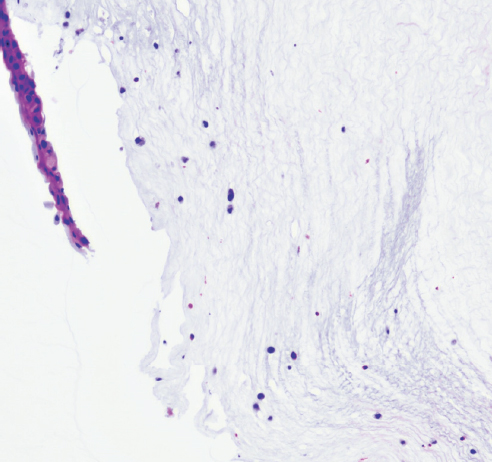

Третий этап эксперимента, морфологический анализ роговиц через 3 дня, группа 3

Режим 7. На месте воздействия определяется дефект — участок стромы роговицы, не покрытый эпителием. Глубина поражения не превышает 1/4 толщины стромы. Волокна стромы лежат рыхло. В области дефекта между коллагеновыми волокнами находятся единичные фиброциты, при этом выявляется умеренное число эозинофилов. Область дефекта окружена уплощённым эпителием, у которого клетки базального слоя очень низкие, ядра в них лежат горизонтально, однако здесь же обнаруживаются небольшие участки утолщения эпителия, в которых клетки лежат неупорядоченно. Строма по краям от дефекта обычного строения, несколько разрыхлена. Десцеметова мембрана и энодотелий без изменений (рис. 16).

Рис. 16. Фрагмент роговицы после воздействия в группе 3. Фульгурация, режим 7. Лейкоциты в строме роговицы. Окраска гематоксилином и эозином. Увеличение ×100

Fig. 16. Fragment of the cornea after exposure in group 3. Fulguration, mode 7. Leukocytes in the stroma of the cornea. Stained with hematoxylin and eosin. Magnification ×100

Сочетание кросслинкинга с фульгурацией позволило получить более компактную структуру передних слоёв стромы роговицы, хорошо проявляющуюся морфологически до глубины 150–200 мкм. По данным литературы известно, что демаркационная линия при проведении оптической когерентной томографии переднего отрезка глаза после кросслинкинга роговицы человека проходит обычно на глубине 300 мкм. Возможно, в нашем исследовании более глубокое уплотнение стромы явно не проявлялось морфологически. Но подобное «уплотнение», по мнению ряда авторов, может уменьшать патологические действия протеолитических ферментов патогенных микроорганизмов на роговицу. По результатам исследования отчетливо видно, что эпителий при комбинированном воздействии в последующем крепче фиксирован к строме, что вероятно можно объяснить более надежными комплексами адгезии за счёт увеличения ковалентных связей из-за проведённого кросслинкинга. По данным эксперимента в первые дни после фульгурации в режиме 7, который является, на наш взгляд, максимально эффективным и при этом безопасным, глубина дефекта роговичной ткани зависит от длительности воздействия, но обычно не превышает 70 мкм. Затем толщина роговичной ткани восстанавливается и уже на сроке около месяца становится относительно равномерной. Таким образом, исходя из данных технической документации прибора и результатов эксперимента, можно сделать заключение, что фульгурация — это прецизионное, контролируемое, щадящее воздействие электротермического характера, позволяющее наносить коагуляты диаметром 0,1 мм2 на глубину около 70 мкм для эрадикации инфекционных агентов при фармакорезистентных прогрессирующих кератитах, когда формирование помутнения при выздоровлении неизбежно.